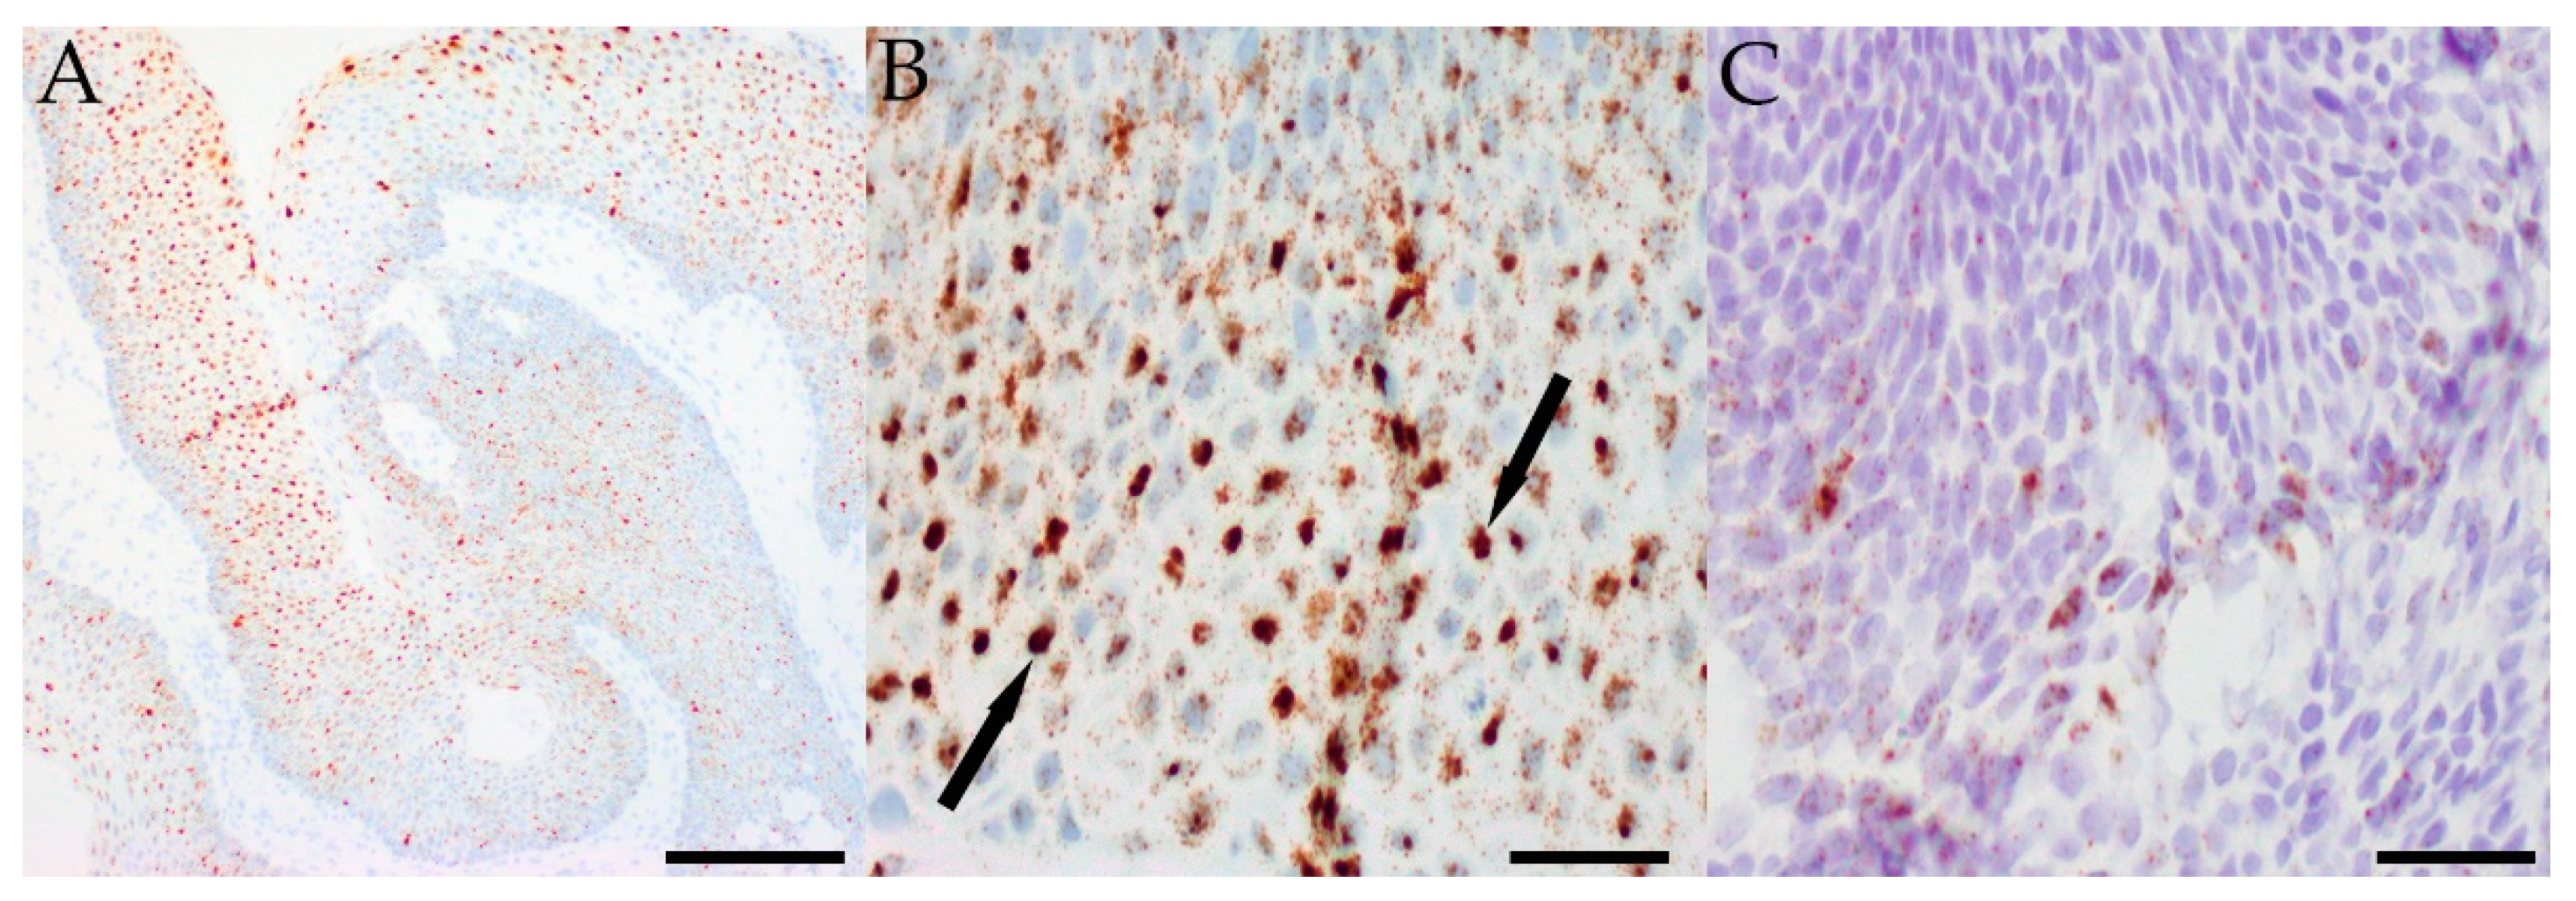

Figure 2.

Representative images of in-situ hybridization showing diffuse low-risk HPV positivity in a papilloma from Case 6 using RNA probes (A) (scale bar: 100 μM). At higher magnification, many nuclei are almost completely filled with smaller dot-like foci of staining (arrows) (B) (scale bar: 25 μM). More focal high-risk HPV positivity in a papilloma from Case 16 using DNA probes (C) (scale bar: 25 μM).